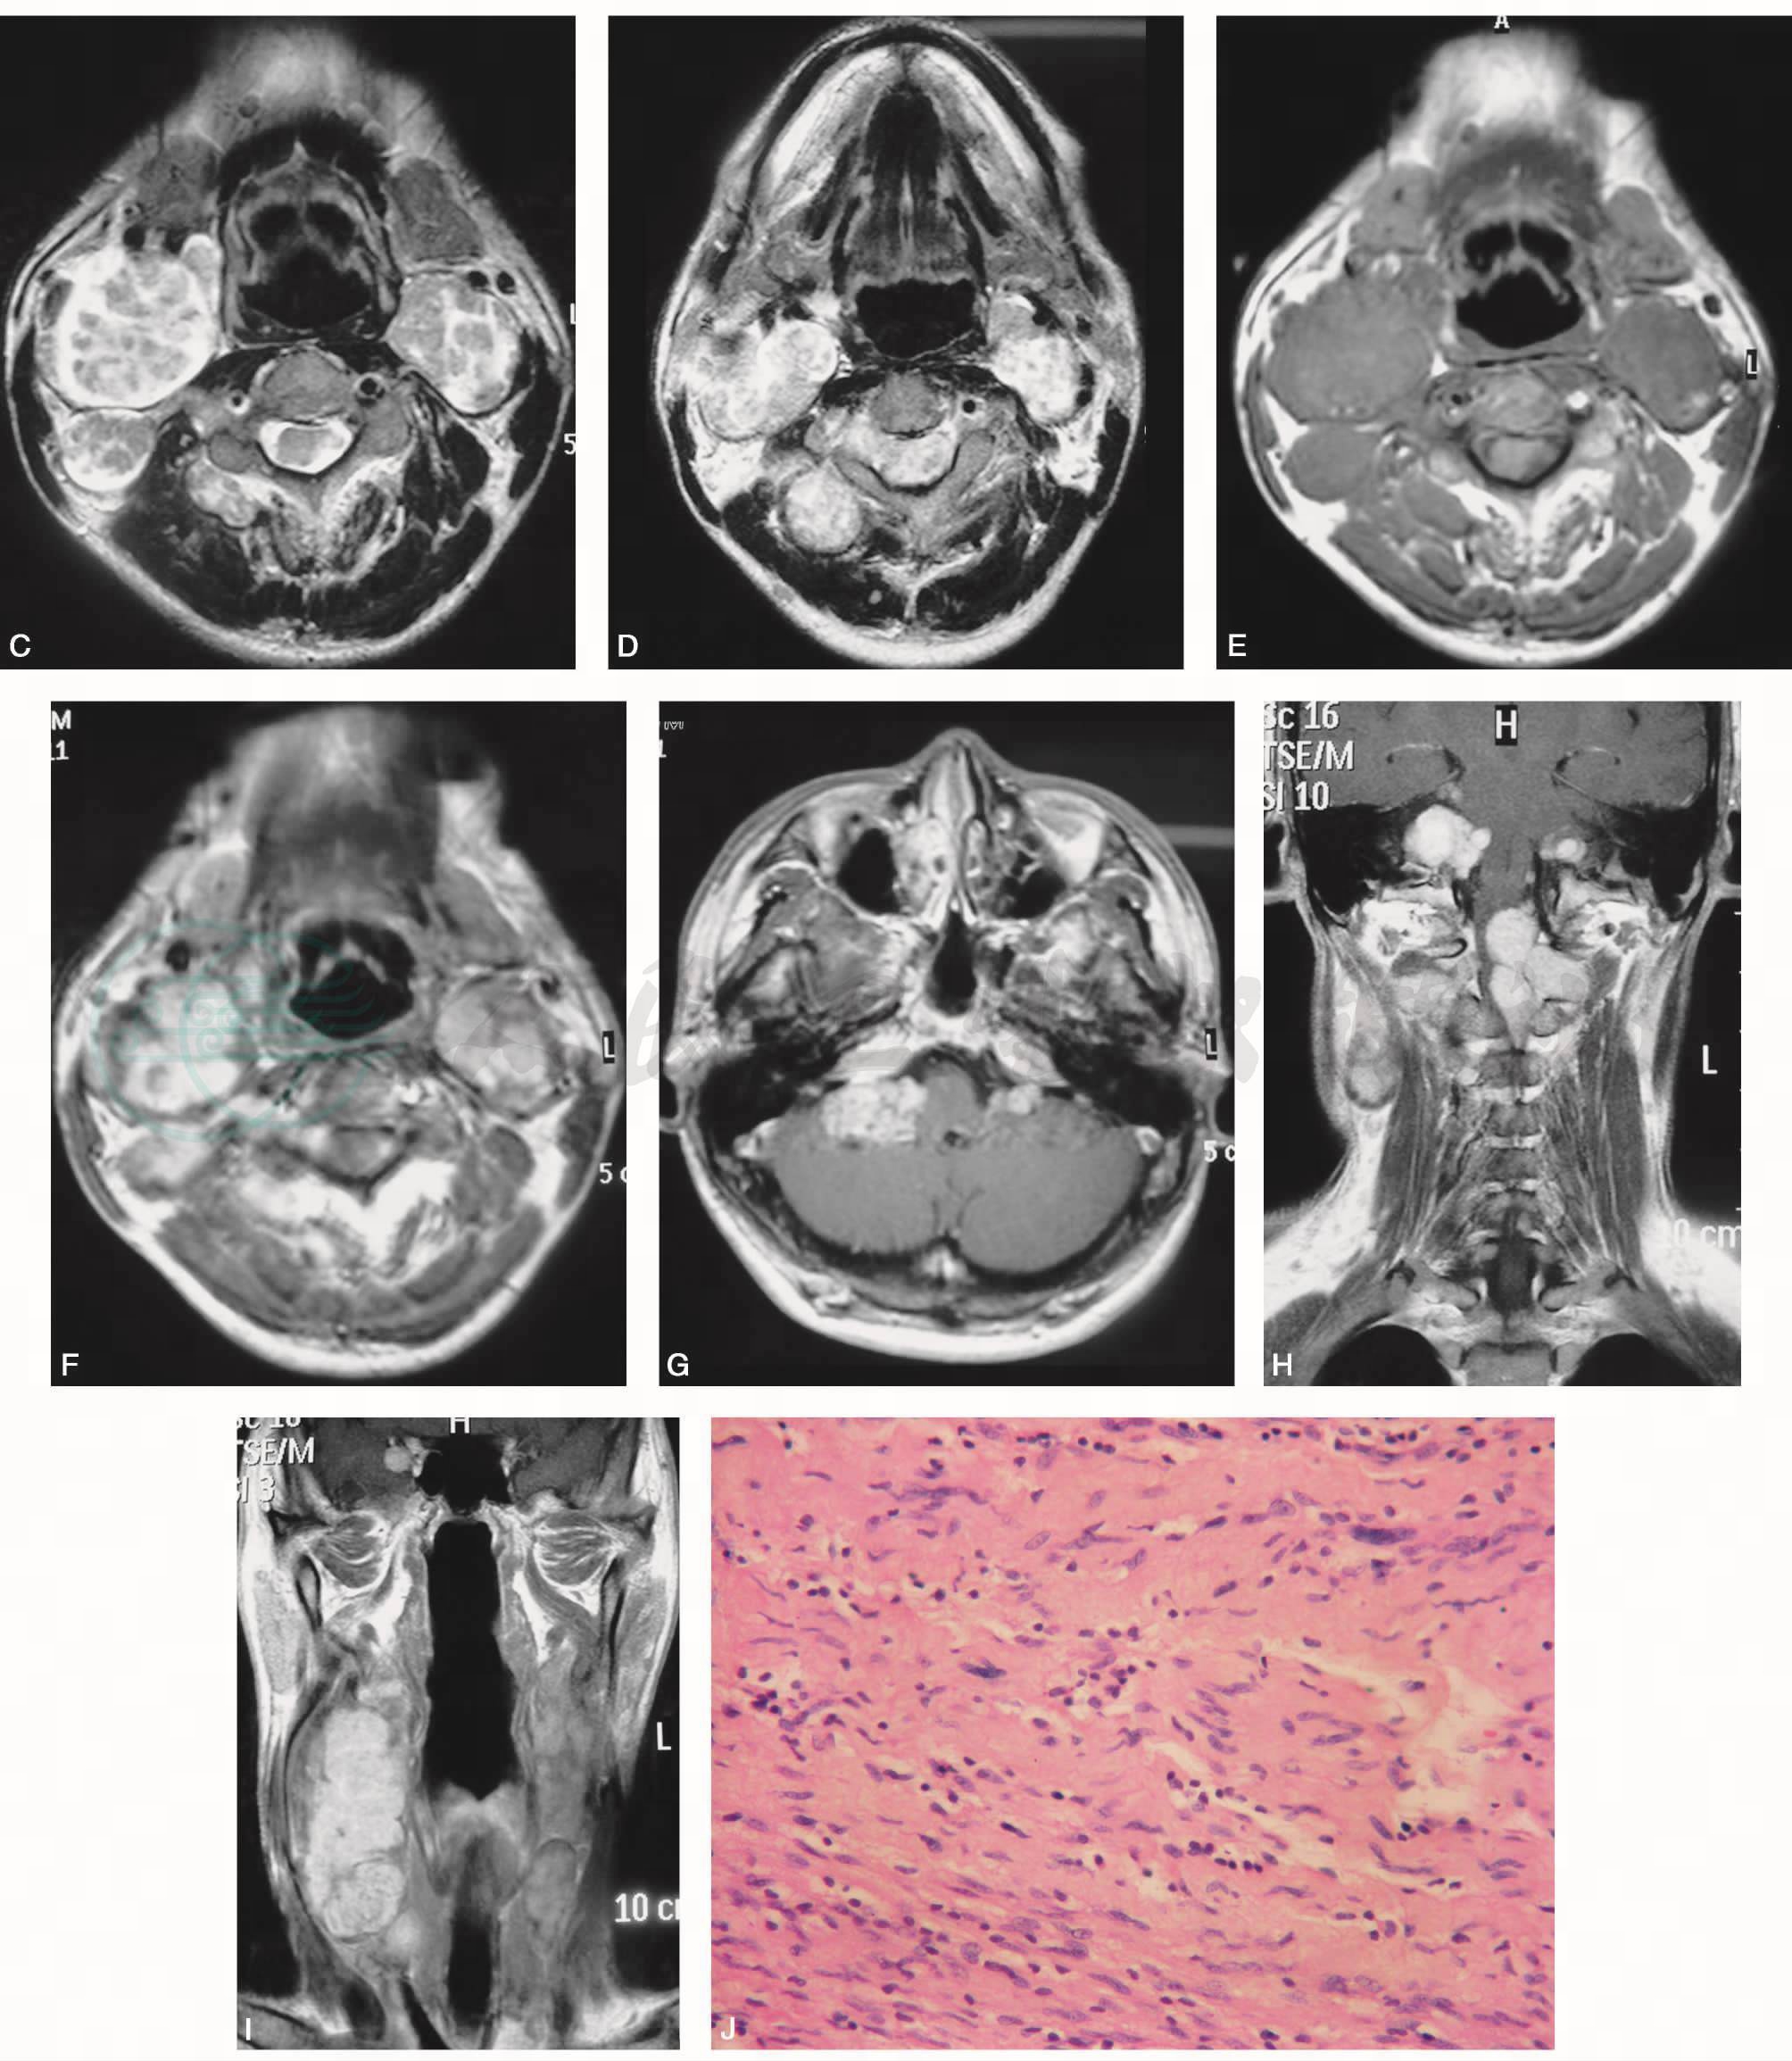

皮肤多发棕色色素斑(图1A、B);T2WI(图1C、D)见双侧胸锁乳突肌深面多发结节、肿物,信号增高,欠均匀,边缘清楚;T1WI为等信号(图1E);增强后结节、肿物强化明显(图1F~I);其中双侧听神经、右侧海绵窦旁可见结节状强化。

图1 颈部多发神经纤维瘤病

A~B.多发棕色色素斑;C~D. T2WI横断位;E. T1WI横断位;F~G. T1WI增强横断位;H、I. T1WI增强冠状位;J. HE×200

右C1/2椎间孔扩大,有一约2.5cm×2cm×2cm硬脊膜外肿物,色黄白,质实,边清,血供一般,与一神经根相连,部分侵入硬脊膜下;枕大孔左右各见一同性质肿物,右侧硬膜下髓外还见两个同性质肿物,均与一神经根相连,分别给予切除。

病理结果:符合神经鞘瘤(图1J)。